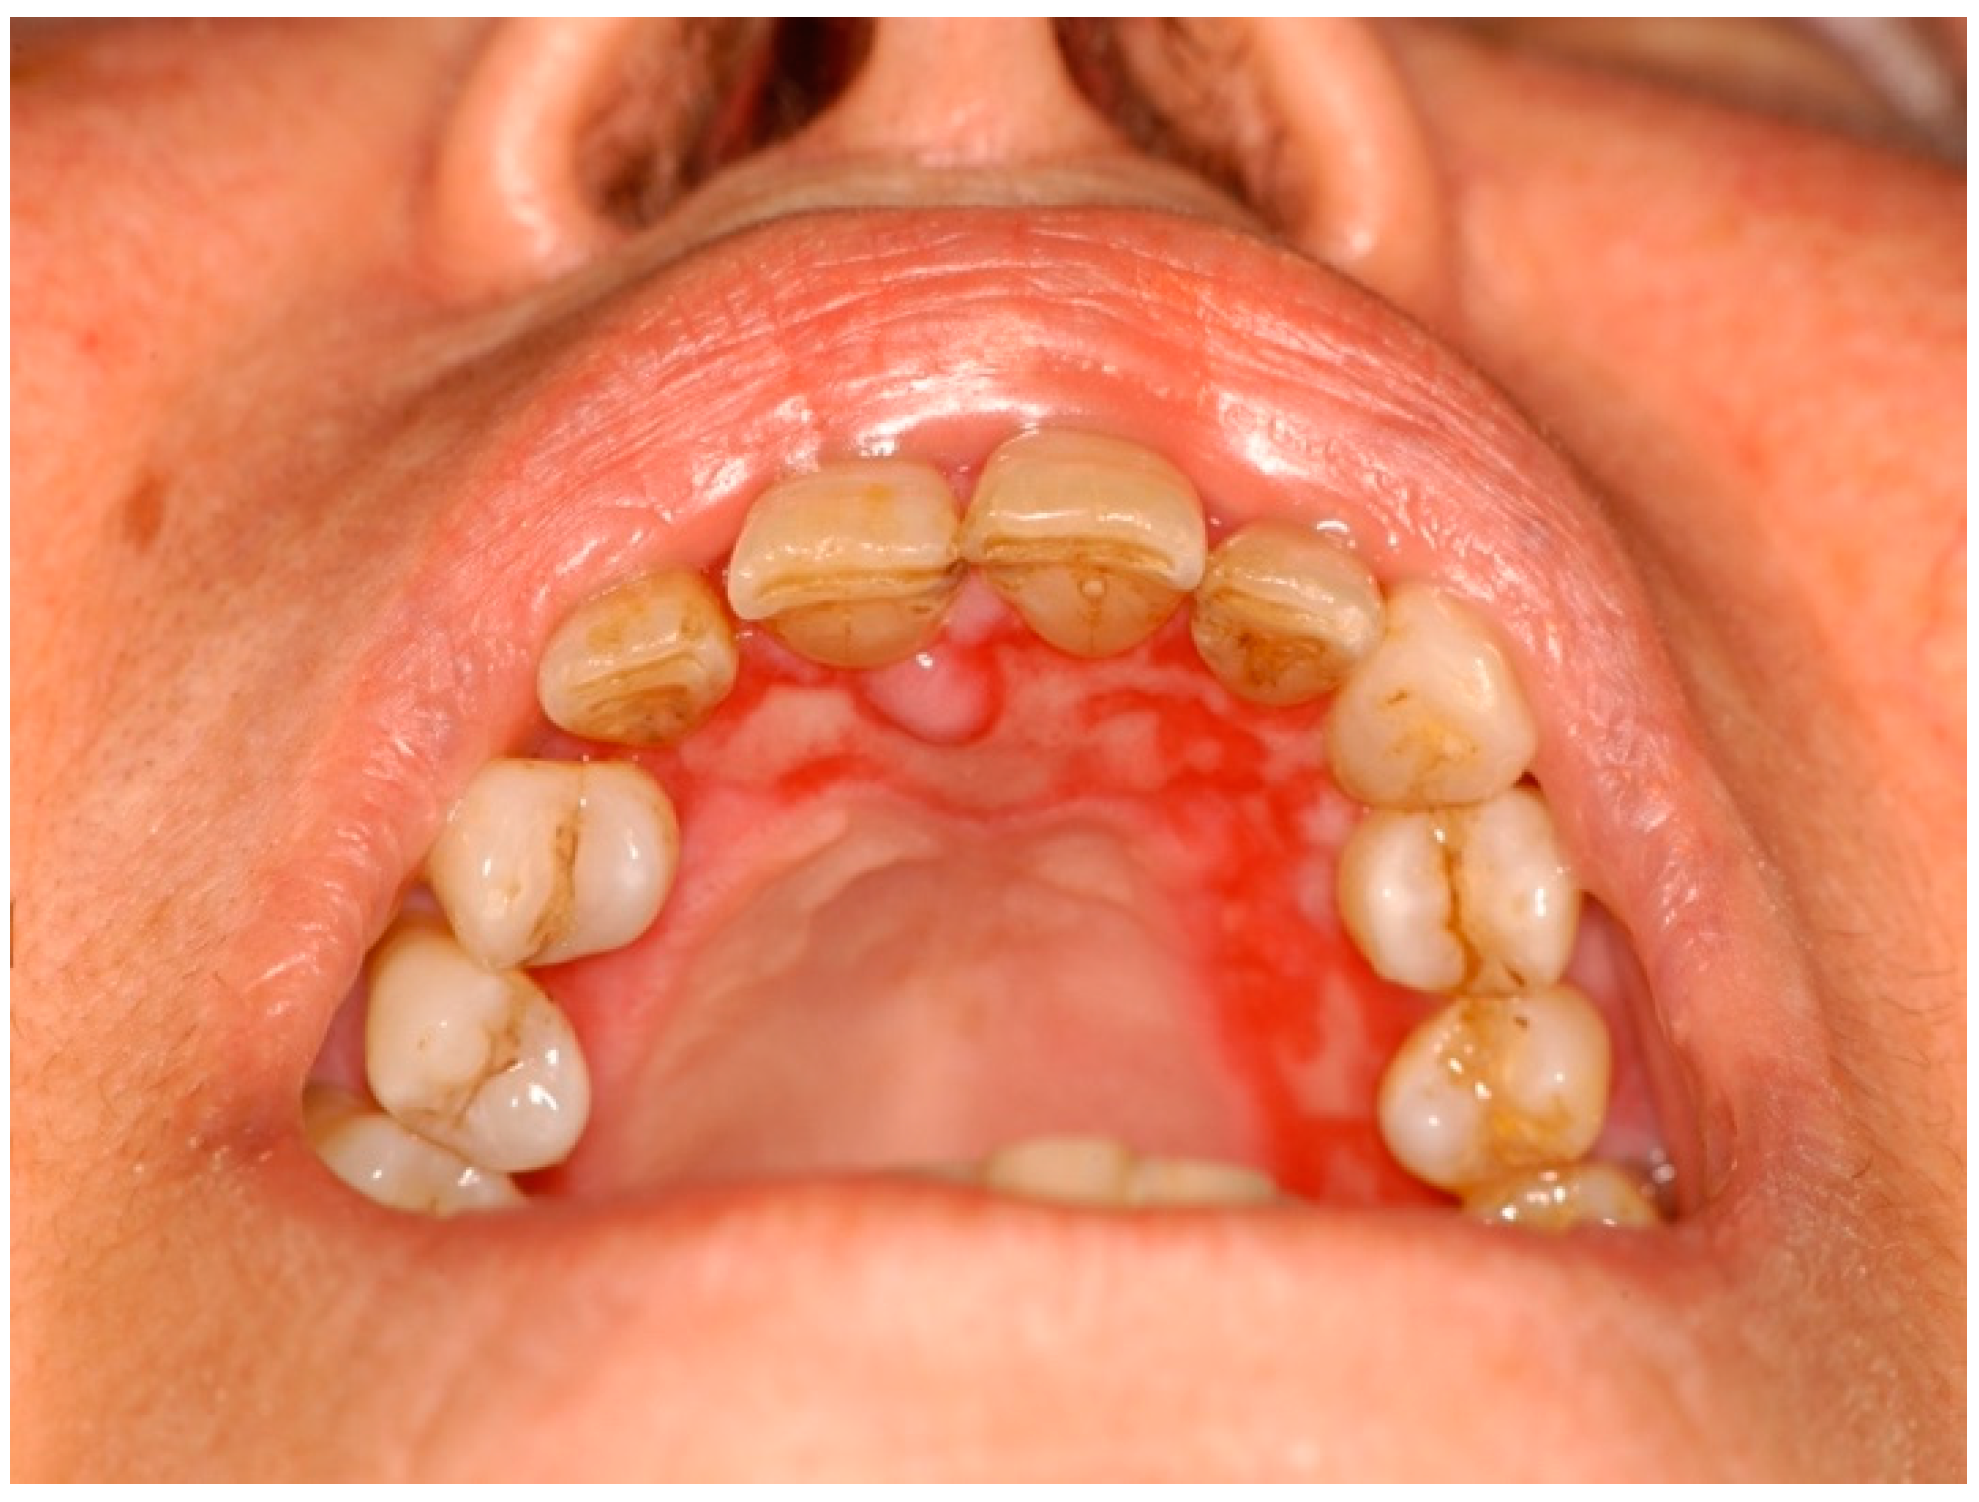

2.1.2. Oral Lichenoid Lesions (OLLs)